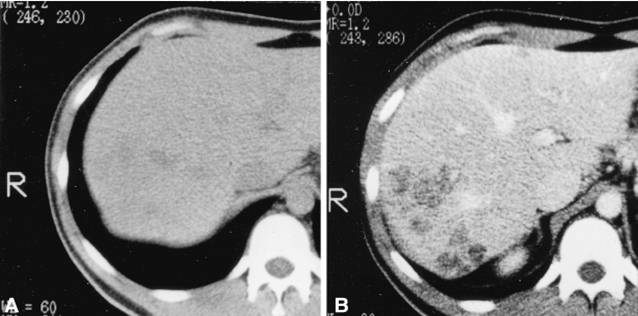

Điều trị sán lá gan lớn hiện nay ở Việt Nam là các bác sỹ đang sử dụng loại thuốc đặc trị triclabendazole với nhiều biệt dược có mặt trên thị trường (Egaten®, Lesaxys® hay Deworm®). Đây là một loại thuốc khá an toàn trên mọi đối tượng sử dụng khi điều trị sán lá gan lớn ở trẻ em và người lớn. Một số tác dụng ngoại ý chỉ là thoáng qua và hầu như các thử nghiệm lâm sàng và thực tế điều trị không thấy tác dụng ngoại ý nào nghiêm trọng.

Thuốc điều trị sán lá gan đặc hiệu loại triclabendazole (TCBZ) dù đã chứng minh rất an toàn trên mọi đối tượng, song các thử nghiệm tên mô hình động vật thí nghiệm cho thấy ít nhiều ảnh hưởng lên phôi thai, đặc biệt ở chuột.

Hình 10

Do vậy, các nhà nghiên cứu khuyên không nên dùng cho phụ nữ đang mang thai với khuyến cáo chống chỉ định tương đối. Nghĩa là, việc điều trị sẽ do bác sỹ chuyên khoa quyết định dựa trên cân nhắc lợi ích và nguy cơ, nếu lợi ích cứu lấy tính mạng người mẹ lớn hơn là nguy cơ từ tác dụng ngoại ý thì có thể quyết định điêu trị cho bệnh nhân đang mang thai, chẳng hạn một số trường hợp thai quá lớn, bệnh nhân quá đau đơn do ổ thương tổn abces từ sán lá gan lớn gây nên, có thể dẫn đến hậu quả sẩy thai, sinh non, tai biến,....

Một số báo cáo đơn lẻ ca bệnh trên thế giới cũng đã chỉ định điều trị thuốc TCBZ cho nhiều ca bệnh sán lá gan lớn trên cơ địa phụ nữ đang mang thai, bất cứ thai kỳ nào cũng có thể và theo dõi không có tai biến hay biến chứng gì cả, đặc biệt trong 3 tháng giữa và 3 tháng cuối rất an toàn.

Trên ca bệnh của vợ em đang mang thai 10 tuần (khoảng hơn 3 tháng), quyết đinh điều trị còn tùy thuộc vào bác sỹ thăm khám cho vợ mình và kết quả xét nghiệm cũng như siêu âm có kích thước như thế nào.

Chẳng hạn, nếu ổ thương tổn lớn mà thai đang quá nhỏ tháng thì nếu đợi đến khi sinh xong mới điều trị thay tiên lượng không tốt….